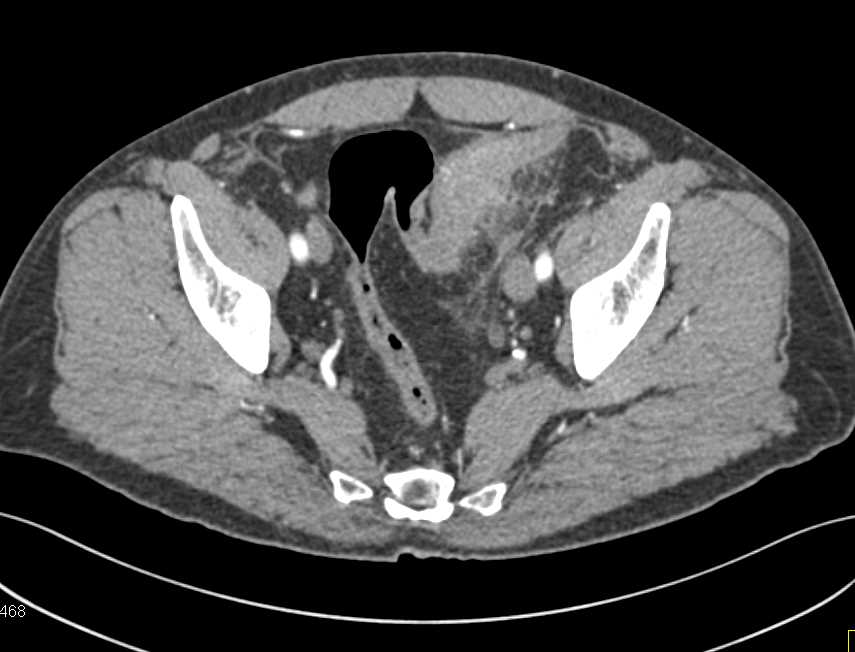

Ischemic Colitis Descending Colon